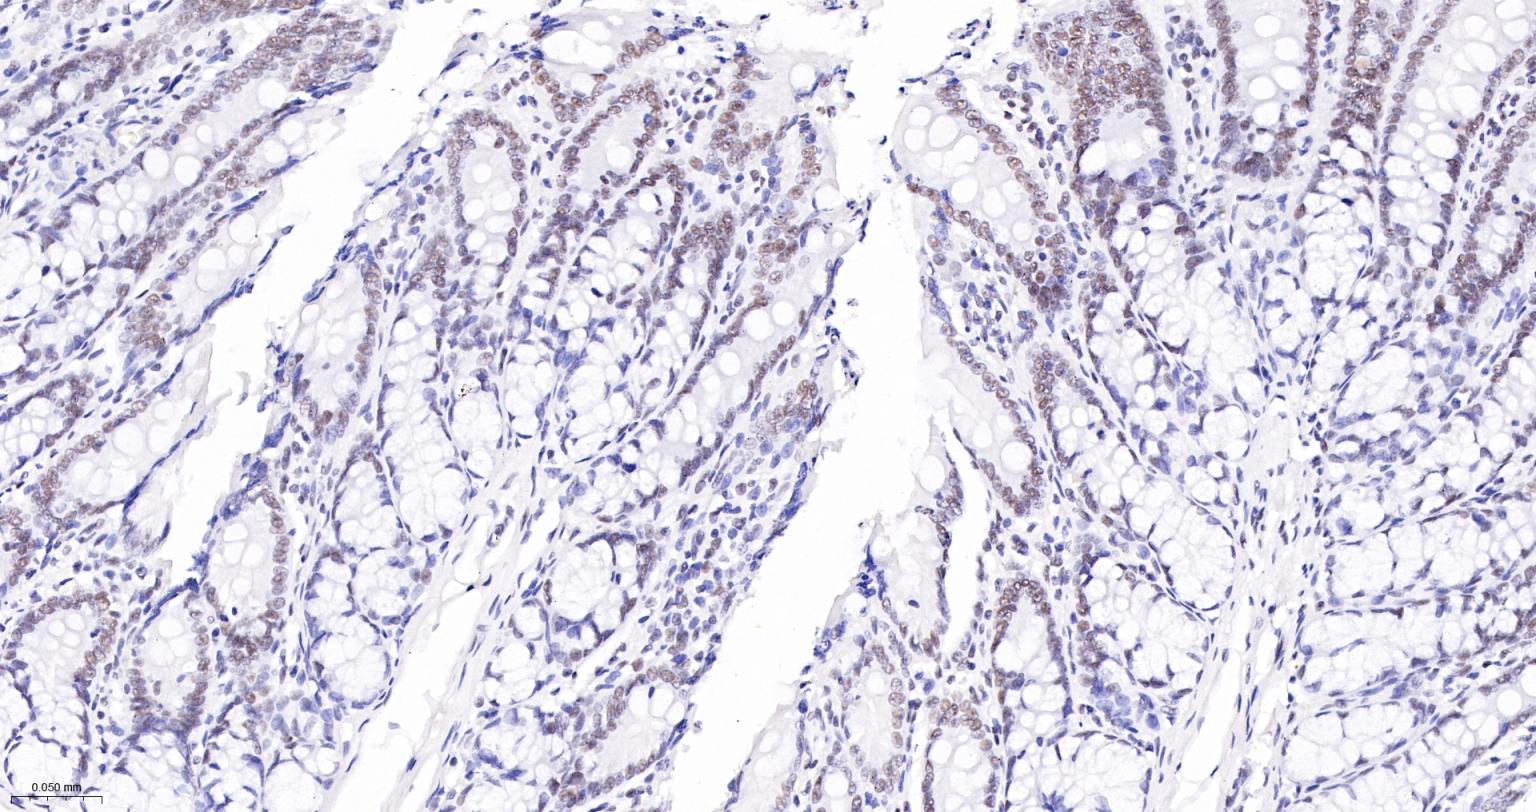

Paraformaldehyde-fixed, paraffin embedded Human Colon Cancer; Antigen retrieval by boiling in sodium citrate buffer (pH6.0) for 15 min; The section was incubated with USP39 Monoclonal Antibody, Unconjugated (bsm-63016R) at 1:200 overnight at 4°C, followed by conjugation to the bs-0295G-HRP and DAB (C-0010) staining.